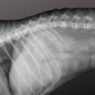

When should I vaccinate my dog? emlabradors